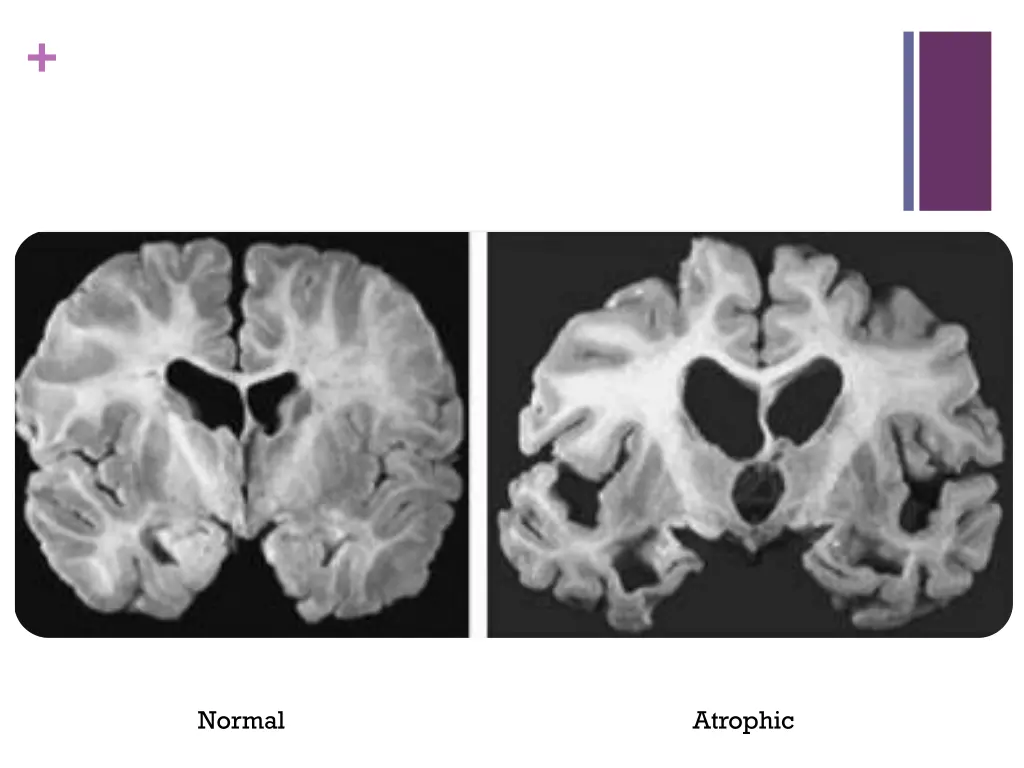

+ Normal Atrophic

+Diagnosis Diagnosis is clinical Rely on history and cognitive/neuropsychological assessments that demonstrates a slowly progressing cognitive disorder which causes impairments in daily life. Brain structure on MRI may demonstrate medial temporal atrophy bilaterally PET scans can demonstrate decreased metabolism in temporal and parietal regions Cerebrospinal fluid might show low Amyloid beta, and elevated Tau (not specific)